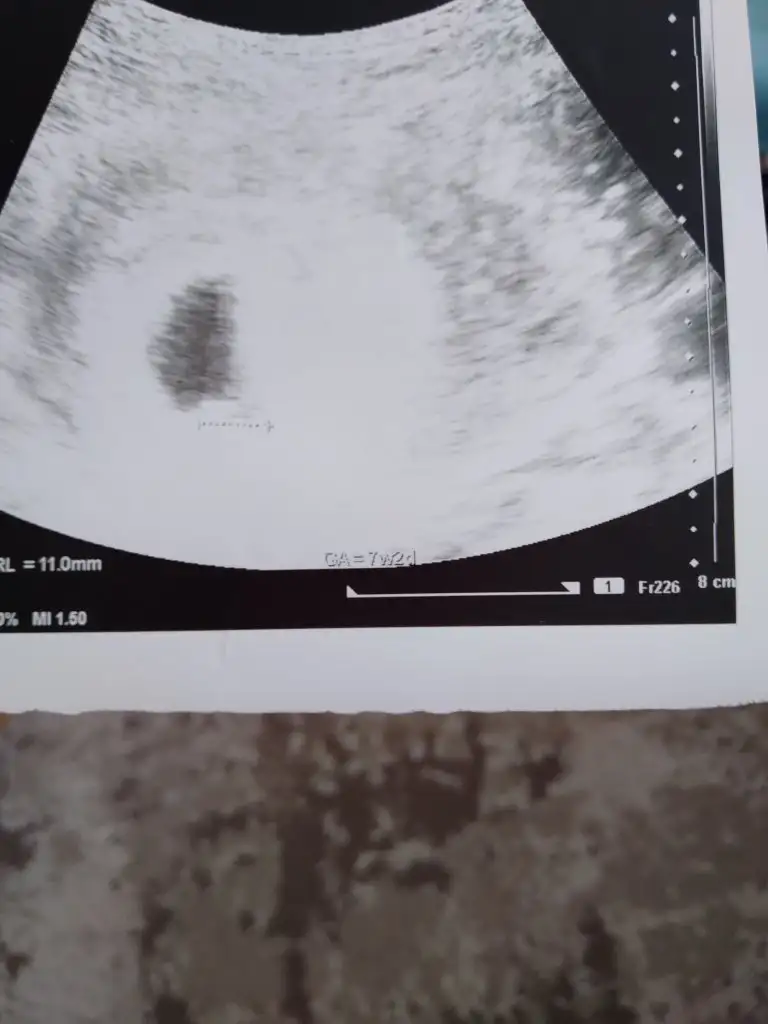

kuzucum karından mı yazmamışsınEki Görüntüle 3034761 8 haftalık, arkadaşım için tahmin alabilir miyim![]()

bebek olması şart kuzumAy ben de atacagim asiri merak ettim ama benim bebek daha görünmedi olur mu ?

2 hafta sonra tekrar gideceğim o zaman atayımbebek olması şart kuzum![]()